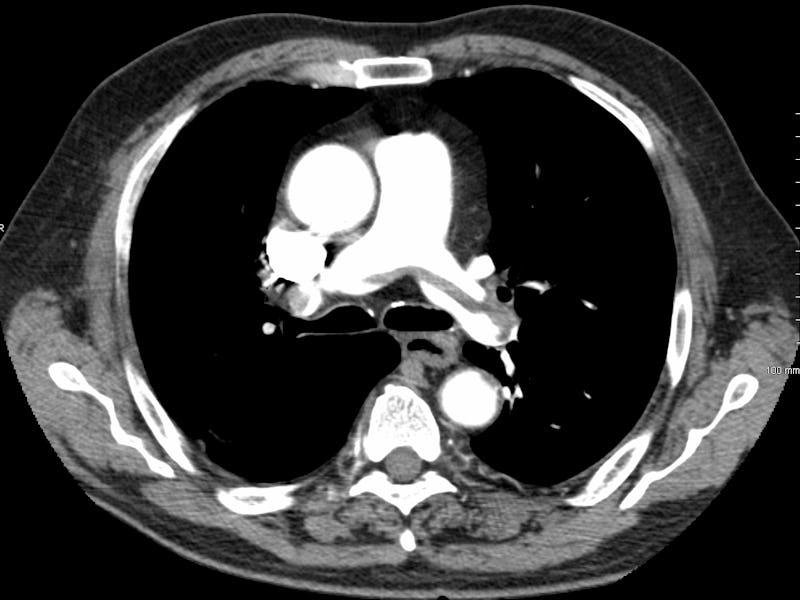

A pulmonary embolism is often caused by blood clots in the legs that travel to the lungs. This is not uncommon among travelers, seeing as blood clots can form in the deep veins (veins below the surface that are not visible through the skin) when the traveler is sitting for long periods of time. Known as venous thromboembolism (VTE), these deep-vein blood clots have become a systemic problem in air travel, as noted in various studies published with the U.S. National Library of Medicine. Passengers who notice swelling in the feet and legs when they are on a long flight should be especially cautious. These blood clots may dissolve on their own or break off and travel to the lungs, which is what happened to Oswell.